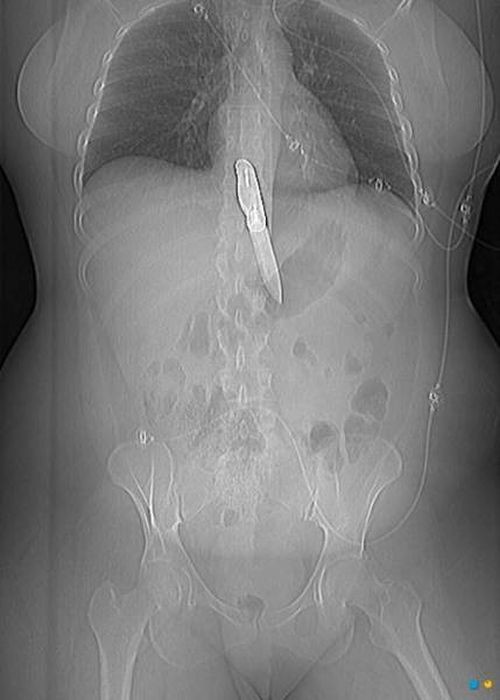

Предметы, которые не очень хочется видеть внутри себя

Под рентгеновскими лучами порой видны не только внутренние органы и кости, но и инородные тела, попавшие в организм

Истории попадания этих предметов в организм могут быть самыми невероятными и запутанными, но больше всего медиков интересует процесс их извлечения, впрочем, в этом заинтересованы и сами пациенты, допустившие нечто подобное со своим телом.